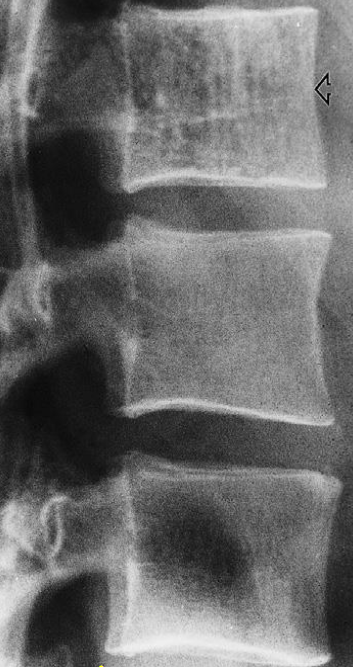

Modality X-ray lumbar spine (lateral view)

Findings Anterior displacement of L4 on L5 is visible. In addition, there is degenerative disk disease with narrowing of the L4–L5 disk space.

Diagnosis Disc Space Narrowing e.g. degenerative disc disease; Associated with endplate sclerosis and osteophytes